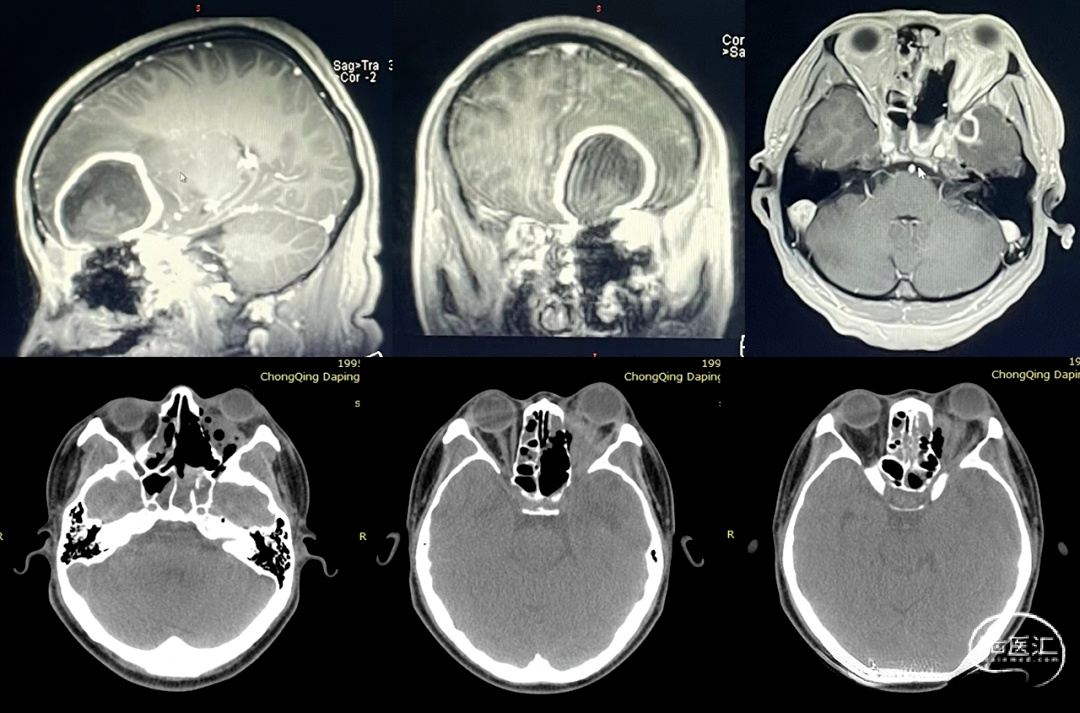

2022.03.02 MR/CT:左侧额叶脓肿形成,直径4cm,颞叶小脓肿,直径约1CM。蝶窦内局限性积液,左侧眼眶内组织肿胀,考虑脓肿形成。可见脓肿与前颅底薄弱部位关系密切。

非功能区脑脓肿是否手术治疗,一般根据脓肿直径,一般认为直径>3cm者,需要手术引流或切除。患者额叶脓肿直径为4cm,占位明显,手术指征明确;但其源于鼻窦,及眼眶内感染,必须同时处理,否则颅内脓肿必将死灰复燃。而脓肿能够波及颅内,说明颅底骨质薄弱或有所缺损,从患者影像上也能够证实这一点。

2022.03.04 次冠状入路额叶脓肿切除+前颅底修补术

遂于3月4日,在双镜联合下行额叶脓肿切除及眶内脓肿引流术。上图可见额叶脓肿切除后,前颅底薄弱区域,以额部骨膜瓣翻折进行修补。

2022.03.04同期鼻内镜下视神经管减压+眶内脓肿切开引流术

可见首次手术鼻窦开放充分,引流效果好。但视神经管及眶壁骨质大部完整,眶骨膜完好,切开眶骨膜,方见脓肿。说明首次手术并未开放眼眶及视神经管,导致引流不畅,治疗效果不佳。术后患者恢复良好,随访期间,眼球凸出逐渐恢复,但视力无明显改善。